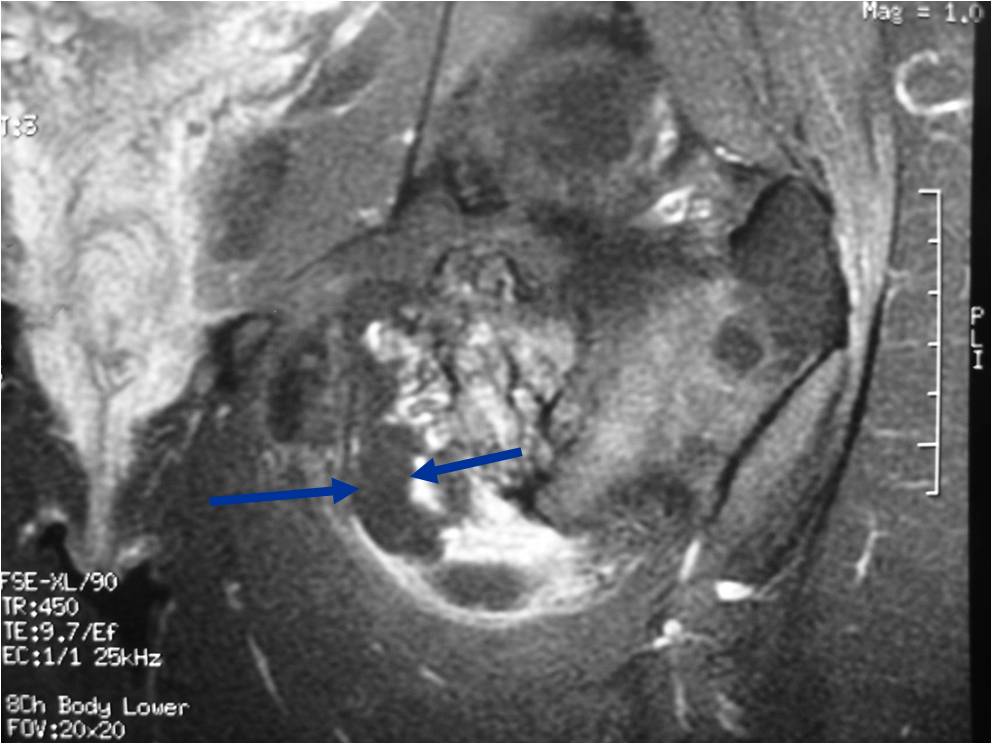

MRI: Secondary Chondrosarcoma of Proximal Femur: Thick Cartilage Cap (>2cm)

- Best test for evaluating thickness of cap and surrounding bursa

- Intermediate T1W Images

- High Intensity T2W Images because of fluid content